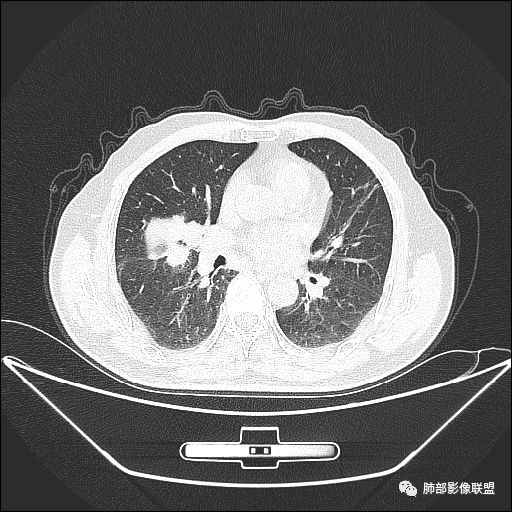

住院4天后行胸部增强CT

右肺中叶外侧段管腔阻塞、实性病变,病灶边缘光滑,可见分叶,肺门及纵隔可见肿大淋巴结,并可见钙化。增强可见病灶内多发低密度区。

胸CT:跨叶大肿块,主体在中叶,右中叶外侧段支气管阻塞,病灶部分边缘膨隆,可见分叶,部分边缘平直,肺门及纵隔可见肿大淋巴结。增强病灶不均匀强化,延迟强化明显,病灶内多发低密度区,内见血管飘浮,部分血管变细、模糊。考虑:恶性病变可能性大,大细胞?淋巴瘤?鉴别慢性肉芽肿性病变。

右肺中叶软组织肿块,外围向内生长,叶间胸膜向前内移位,肿块近肺门侧跨叶,中叶外侧段支气管截断,密度不均匀,双侧肺门及隆突下见肿大淋巴结,增强后呈中度不均质强化,肺动脉供血,多发坏死区,边界尚清,坏死区域内见结构,结合病史考虑恶性,鉴别诊断1结核,爬行征是沿支气管树分布,外宽,内窄,周围有卫星灶,内气管狭窄后扩张,此例沿叶间胸膜长轴分布,气管有截断,不典型。2炎性肉芽肿,符合的地方下方层面增强后延迟性轻度环形强化,不符临床无发热等急性感染病史,实验室指标不符,病灶周围渗出及慢性炎性改变有,不明显。

吴婧老师和南边老师都对该病例进行了深入分析。从支气管管壁的增厚,支气管狭窄后扩张,支气管粘液栓,病灶形态,到病灶不均匀强化及坏死彻底,到周边病灶及肺组织空气的潴留,加之纵隔内淋巴结肿大伴钙化等等,都支持慢性炎性病灶,尤其是结核。

墨西哥仙人掌征---结核        影像上结核灶,粗大的均匀枝干,推测是支气管囊状扩张引起的,在非支气管区,形成圆形坏死囊群;如果这些坏死比较稀薄,又遇到扩张支气管,就会形成粗大的“墨西哥仙人掌”。结核引起的支气管近端炎症纤维化,可以造成支气管阻塞,从而将干酪样坏死物封堵在管腔内。仙人掌主干内部应该是干酪为主,稀薄的,具有流动性,时间久了会出现钙化。

结核坏死与鳞癌鉴别有一点是结核坏死没有方向性,鳞癌有。鳞癌靠近支气管近端部分,血供容易维持,不易坏死,所以坏死靠外侧。而结核干酪样坏死,把一定体积的流动性坏死物,包裹起来,什么形状最省料?坏死物包裹,表面积最省的自然是圆球形,而遇到支气管,坏死物一多,就把支气管撑大了。包裹物是就地取材,扩张的支气管就成了包裹结构。